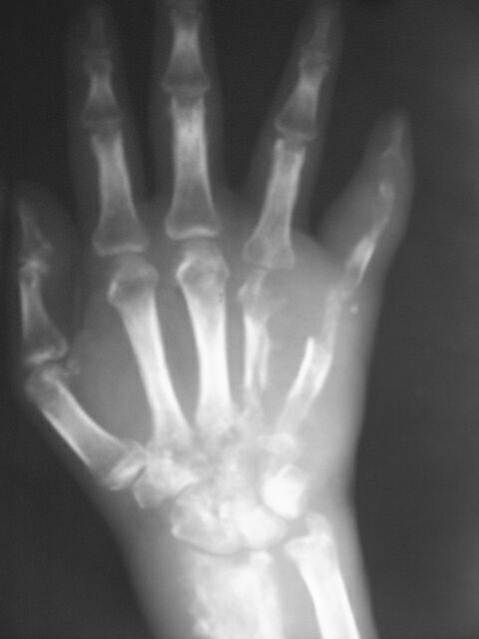

Infective arthritis